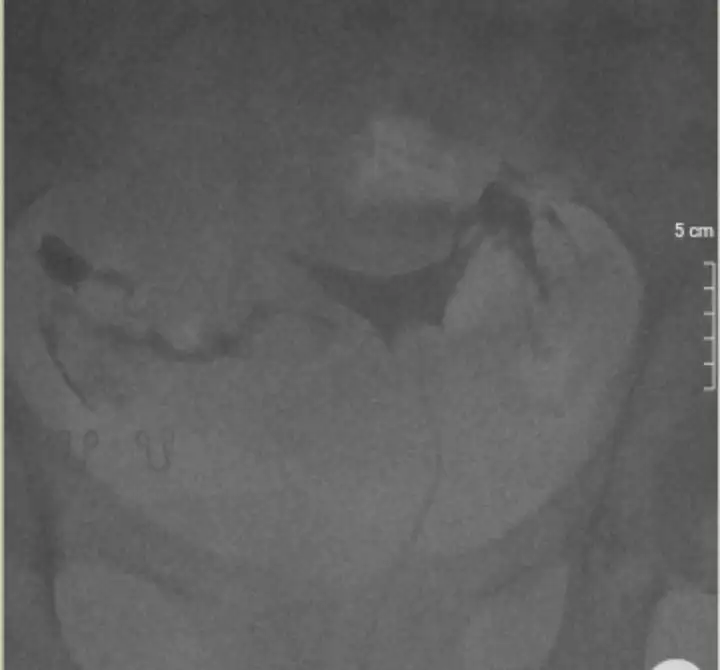

en net bu galiba canımo siyah görünen kısımlar var ya canım onlar ilaç ama daha net bi görüntü yok mu

canım rahim filminde kist miyom onlar belirlenmez. rahim filminde ilaçla tüplere bakılıyor sadece. ama farklı bi durum olsa yazar zaten sonucundaPeki herhangi bir sıkıntı olsaydı yazardı demi filmde mesela kist mym polip gibi yada yumurtalık şekliyle alakalı

görüntü tam net değil baya mat duruyoren net bu galiba canım

mat derken canımgörüntü tam net değil baya mat duruyor

Bak canım benim görüntüler bu şekilde. Seninkide böyle olması lazımmat derken canım

Sonucunda yazıyormuydu polip göründüğü canımTüpler açık ama tek görüntü bu olmamalı bir kaç resim ve video şeklinde vardı benimkinde . Benim hsg de polip görülmüştü sonra alındı.